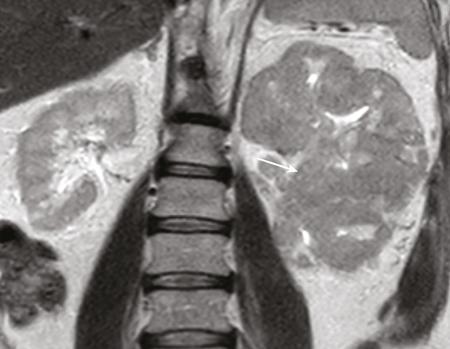

IMAGING OF RENAL MALIGNANCIES IN ADULTS Aparna Katdare, Palak Bhavesh Popat, Nilesh P. Sable, Ganesh Bakshi, Suyash Kulkarni Detection of renal masses has increased remarkably in recent times owing to wide-spread use of cross-sectional imaging. Imaging plays an important role in characterizing renal masses and is indispensable in treatment planning in renal malignancies. The most commonly encountered malignant renal masses in practice include renal cell carcinoma (RCC), urothelial carcinoma, lymphoma and metastases. Urothelial carcinoma and lymphoma have been covered in detail in separate chapters. RCC constitutes nearly 90% of all renal malignancies with a higher incidence in North America and Europe than India, Africa and China. With an increase in the number of cross-sectional studies performed, especially in Western population, the incidental diagnosis of RCC has increased in recent times, with such incidentally diagnosed lesions presenting at earlier stages with better prognosis and reduced rates of recurrence. The median age of presentation of RCC is 64 years according to the Surveillance, Epidemiology and End Results (SEER) program database and almost a decade earlier in Indian population, with a definite increasing risk of RCC with increasing age. Males are affected about 2–3.5 times more than females. In the Indian population, patients have been seen to present at a later stage as compared to the Western population. Amongst the various postulated risk factors, there is convincing evidence that smoking, hypertension, obesity and acquired renal cystic disease increase the risk of RCC. Alcohol intake and physical activity have been found to be associated with reduced risk of RCC. Trichloroethylene and cadmium exposure have been postulated as likely causes as well. Two to four per cent of RCCs are hereditary, with association of various genetic disorders such as Von Hippel Lindau (VHL) syndrome, hereditary papillary renal carcinoma, hereditary leiomyomatosis RCC, Birt-Hogg-Dube syndrome, chromosome 3 translocation and tuberous sclerosis (TCS1, TCS2). The WHO classification of 2016 (Table 11.25.1.1) stratifies tumours of the kidney into different subtypes based on cytoplasmic and architectural features, tumour location, background renal disease and molecular alterations. Clear cell renal cell carcinoma Multilocular cystic renal neoplasm of low malignant potential Papillary renal cell carcinoma Hereditary leiomyomatosis and renal cell carcinoma-associated renal cell carcinoma Chromophobe renal cell carcinoma Collecting duct carcinoma Renal medullary carcinoma MiT family translocation renal cell carcinomas Succinate dehydrogenase-deficient renal carcinoma Mucinous tubular and spindle cell carcinoma Tubulocystic renal cell carcinoma Acquired cystic disease-associated renal cell carcinoma Clear cell papillary renal cell carcinoma Renal cell carcinoma, unclassified Papillary adenoma Oncocytoma 8310/3 8316/1a 8260/3 8311/3* 8317/3 8319/3 8510/3a 8311/3a 8311/3 8480/3a 8316/3a 8316/3 8323/1 8312/3 8260/0 8290/0 Metanephric adenoma Metanephric adenofibroma Metanephric stromal tumour 8325/0 9013/0 8935/1 Nephrogenic rests Nephroblastoma Cystic partially differentiated nephroblastoma Paediatric cystic nephroma 8960/3 8959/1 8959/0 Clear cell sarcoma Rhabdoid tumour Congenital mesoblastic nephroma Ossifying renal tumour of infancy 8964/3 8963/3 8960/1 8967/0 Leiomyosarcoma Angiosarcoma Rhabdomyosarcoma Osteosarcoma Synovial sarcoma Ewing sarcoma Angiomyolipoma Epithelioid angiomyolipoma Leiomyoma Haemangioma Lymphangioma Haemangioblastoma Juxtaglomerular cell tumour Renomedullary interstitial cell tumour Schwannoma Solitary fibrous tumour 8890/3 9120/3 8900/3 9180/3 9040/3 9364/3 8860/0 8860/1a 8890/0 9120/0 9170/0 9161/1 8361/0 8966/0 9560/0 8815/1 Cystic nephroma Mixed epithelial and stromal tumour 8959/0 8959/0 Well-differentiated neuroendocrine tumour Large cell neuroendocrine carcinoma Small cell neuroendocrine carcinoma Phaeochromocytoma 8240/3 8013/3 8041/3 8700/0 Renal haematopoietic neoplasms Germ cell tumours The morphology codes are from the International Classification of Diseases for Oncology (ICD-O) {917A}, Behaviour is coded/0 for benign tumours; /1 for unspecified, borderline or uncertain behaviour; /2 for carcinoma in situ and grade III intraepithelial neoplasia; and /3 for malignant tumours. The classification is modified from the previous WHO classification (756A), taking into account changes in our understanding of these lesions. aNew code approved by the IARC/WHO Committee for ICD-O. Of these, the most common entity is the clear cell subtype, while papillary and chromophobe subtypes are less common. The different subtypes show varied biological behaviour, treatment response and prognosis. The 2017 guidelines by American Urological Association (AUA) as well as 2019 guidelines by European Society of Medical Oncology (ESMO) recommend multiphase cross-sectional imaging by either CT or MRI for renal mass characterization and staging. AUA 2017 guidelines recommend renal mass characterization on the basis of tumour complexity, contrast enhancement and presence or absence of fat. MRI has an upper hand over CT in characterizing subtle mass enhancement, cystic lesions and lesions less than 2 cm. ESMO recommends contrast-enhanced CT study of the chest, abdomen and pelvis for renal mass staging. Bone scan and brain CT or MRI can be considered if indicated by clinical or laboratory investigations. For characterization of renal masses, a multiphase CT or MRI study is recommended. CT study constitutes an unenhanced study followed by contrast injection and acquisition of corticomedullary phase at 40 seconds, nephrographic phase at around 100 seconds and delayed phase at around 5 minutes. MRI protocol includes T2-weighted single-shot fast spin-echo 2D sequences, axial T1-weighted 2D sequence with in-phase and opposed-phase gradient echo imaging, precontrast and postcontrast imaging with a 3D T1-weighted spoiled gradient recalled sequences in corticomedullary phase at 30 seconds, nephrographic phase at 100 seconds, 180–210 seconds and delayed phase imaging at 5 minutes and diffusion-weighted imaging with multiple b-values 0–50, 400–500 and 800–1000 s/mm2. The ACR White Paper on CT imaging of incidental renal mass recommends using the following descriptors for characterizing renal masses: Given the prognostic implications, it is worthwhile for radiologists to know the imaging features that may help discriminate between the common histological subtypes of RCC on various imaging modalities. This is the most common histological type of RCC, accounting for about 70% of cases. These are exophytic tumours with a heterogeneous appearance due to the presence of necrosis, intratumoural haemorrhage, cystic components with septations and calcific foci and hence have a more heterogeneous appearance on cross-sectional imaging than the other subtypes (Fig. 11.25.1.1). Necrosis is seen more often in larger masses and higher tumour grades (Fig. 11.25.1.2). On CT, depending on the tumour composition, these are seen as heterogeneous lesions, show marked contrast enhancement in the corticomedullary phase with washout on nephrogenic phase (Fig. 11.25.1.2). On MRI, these characteristically show high signal intensity on T2W sequences (Fig. 11.25.1.3). The presence of intracytoplasmic fat in the clear cells of the tumour is reflected in the loss of signal in opposed phase images on chemical shift imaging, which is seen in nearly 60% of these tumours. A pseudocapsule may be seen, which is best appreciated on T2-weighted imaging on MRI; the presence of a pseudocapsule has a high negative predictive value for perinephric extension (Figs. 11.25.1.3 and 11.25.1.4). Conversely, larger tumours with higher grades often have interrupted pseudocapsule and hence tend to be irregular, spread into the perinephric fat with renal vein and inferior vena cava (IVC) invasion (Figs. 11.25.1.5 and 11.25.1.6). On diffusion-weighted imaging, clear cell RCCs have been seen to have higher ADC values than nonclear cell RCCs, and lower-grade tumours have been seen to have higher ADC values than higher-grade tumours. The clear cell variant has worse prognosis than the papillary and chromophobe subtypes, presenting at a more advanced stage and being more likely to recur or metastasize (Fig. 11.25.1.7), with lower 5-year survival rates at 44%–69% as compared to 78%–92% for the other two. Papillary RCC comprises about 10%–15% of RCCs. These are slow-growing tumours and hence are well-marginated in contrast to clear cell RCC. As they are hypovascular, their enhancement on CT is significantly less than clear cell RCC (Fig. 11.25.1.8). These show characteristically low signal on T2W images on MRI (Fig. 11.25.1.9). Intracytoplasmic or macroscopic fat is less often seen on MRI imaging as compared to the clear cell variants. Larger tumours tend to be more heterogeneous (Fig. 11.25.1.10). These tumours may sometimes show cystic appearances, mural projections or blood degradation products. Calcifications are more common in papillary variants than clear cell RCC. Multifocality and bilaterality are also more common in these tumours than clear cell variants. These account for about 5% of RCCs. These are less aggressive, more homogeneous and hypovascular lesions than clear cell variants, with intensity of contrast enhancement on cross-sectional imaging being midway between clear cell and papillary variants. They show low to intermediate T2 signals on MRI. A characteristic feature is the presence of a central scar and spoke-wheel enhancement, the latter being a histopathological and imaging similarity between these tumours and oncocytoma (Fig. 11.25.1.11). Other subtypes of RCC are much less common but some may show distinct imaging findings. Multilocular cystic RCCs have excellent prognosis and lack mural nodules within the cystic components, unlike clear cell RCCs with cystic degeneration which show mural nodules. Collecting duct carcinomas, on the other hand, are aggressive tumours with poor prognosis and have medullary origin, and therefore appear similar to transitional cell carcinomas on imaging. Medullary RCCs are associated with sickle cell disease and sickle cell trait and are seen as infiltrating intracalyceal obstructive lesions with associated nodal disease. The imaging work-up of a suspected RCC is aimed at: Localized renal cancer is defined as a disease confined to the renal capsule and refers mainly to stage I and II disease. Nearly 70% of RCCs, especially the lower-stage lesions, are incidentally diagnosed on cross-sectional imaging. Also, amongst incidentally diagnosed renal lesions less than 4 cm in size, about 20% turn out to be benign on histopathology. Asymptomatic incidentally diagnosed small renal masses have an indolent course and better prognosis. Nephron-sparing surgery (NSS) has gathered momentum in recent years due to promising results and prognoses in small lesions. The 2017 AUA guidelines for localized renal masses describe restricted and well-defined indications for radical nephrectomy, bigger role of nephron-sparing procedures such as partial nephrectomy, tumour enucleation and thermal ablation, as well as increasing role for biopsy as well as active surveillance of such lesions. Hence, imaging findings in these lesions become critical in charting management of these patients. The imaging features of common histopathological subtypes of RCCs have already been discussed above. Signal intensity on T2W images and corticomedullary phase enhancement have been seen to be independent predictors of clear cell and papillary RCCs. Further, T2 signal homogeneity can be a predictor for slower growth rate. Hence, in general, multiparametric MRI studies have been shown to be effective in small renal mass characterization and can subsequently guide decisions regarding biopsy, surgery or surveillance. CT is a good alternative in patients with contraindication to MRI. For cystic renal lesions, the Bosniak classification, which stratifies the risk of neoplasia in cystic renal lesions based on the complexity of their appearance (wall thickness, septations, solid component), can be used effectively to decide further course of management. The Bosniak classification originally applies to CT findings but can logically be extrapolated to MRI, USG and Contrast Enhanced Ultrasound (CEUS) as well. Bosniak I and II cysts are benign while Bosniak IIF, III and IV cysts show progressively increasing risk of neoplasia. Given the more indolent course of cystic RCCs as compared to solid lesions and possible complications of interventions, lately there has been a case for even the type III and IV cysts, which previously would be operated, to be followed up, especially if patient has existing comorbidities or if the solid component is minimal. Initial follow-up would be at 6 months, followed by annual imaging. AUA 2017 guidelines recommend considering renal mass biopsy if haematologic, metastatic, inflammatory or infectious aetiology is suspected. Once the need for surgery is established in a localized disease, NSS may be considered for stage Ia and Ib disease. To predict perioperative outcomes in NSS, various scoring systems have been proposed for preoperative renal mass evaluation, such as R.E.N.A.L. nephrometry score, PADUA score (Preoperative aspects and dimensions used for anatomical classification), C-index method and mathematical tumour contact surface area (CSA). The popular R.E.N.A.L. nephrometry score takes into account various tumour descriptors that help decide the technical feasibility of NSS and predict surgical outcomes. These include tumour radius, exo/endophytic location, nearness to collecting system or renal sinus, anterior/posterior location and location with reference to polar lines. These descriptors need to be commented upon diligently while reporting renal masses (Table 11.25.1.4). Higher scores are seen to correlate with ischaemia time, postoperative urologic complications, higher grade and mortality. These include organ-confined tumours more than 7 cm in size, or tumours of any size which show regional nodal involvement and/or invasion of perinephric tissues but confined to Gerota’s fascia. These include renal vein and IVC invasion (luminal and mural). Generally, radical nephrectomy is recommended by the National Comprehensive Cancer Network (NCCN) in stage II and III RCCs. Both CT and MRI are effective in diagnosing locally advanced disease in RCC. The loss or interruption of pseudocapsule is seen in more infiltrative and aggressive disease and is best seen on MRI. Local infiltration may be in the form of contiguous spread to perinephric tissues or discrete deposits in perinephric fat (Fig. 11.25.1.15). IVC or renal vein invasion could be in the form of intraluminal thrombosis or invasion of the vessel wall and have implications on surgical approach and outcomes. Tumour thrombus can be distinguished from bland thrombus by confirming vascularity within the thrombus on imaging. Doppler evaluation, CEUS, CT and MRI can all be helpful for the same. MRI is better than other modalities for venous evaluation, especially for mural invasion and IVC invasion (Figs. 11.25.1.16 and 11.25.1.17). Right-sided tumours, anteroposterior IVC diameter of 2.4 cm or more at the level of renal hilum and complete IVC occlusion at this level are associated with higher risk of IVC resection. About 16% of patients with RCC have metastases at diagnosis and about 20%–30% of patients operated for local disease develop recurrence or metastases at a later date. The recurrent disease occurs most commonly within 3 years of diagnosis and uncommonly even later in young patients or large tumours. The most common sites of metastases from RCC are lungs, liver, bones, nodes, adrenals and brain. CT scan is the preferred modality for primary staging and surveillance for metastases because of its widespread availability and versatility for diagnosing bone and soft tissue lesions. MRI is preferred for looking for recurrence in postablative lesions, wherein these are seen as new enhancing lesions or show increase in the size of preexisting enhancing components. 18FFluorodeoxyglucose – Positron Emission Tomography (PET)/CT and PET/MRI may be helpful to look for metastatic disease as well. 18FSodium fluoride – PET/CT has been found to be better than CT and bone scan in detecting osseous metastases. RCC is a relatively radiation-resistant tumour, and treatment options tilt in favour of surgical procedures for localized and locally advanced diseases. For metastatic disease, post-risk assignment, the treatment has to be planned. Treatment can be offered as per size and the clinical stage.